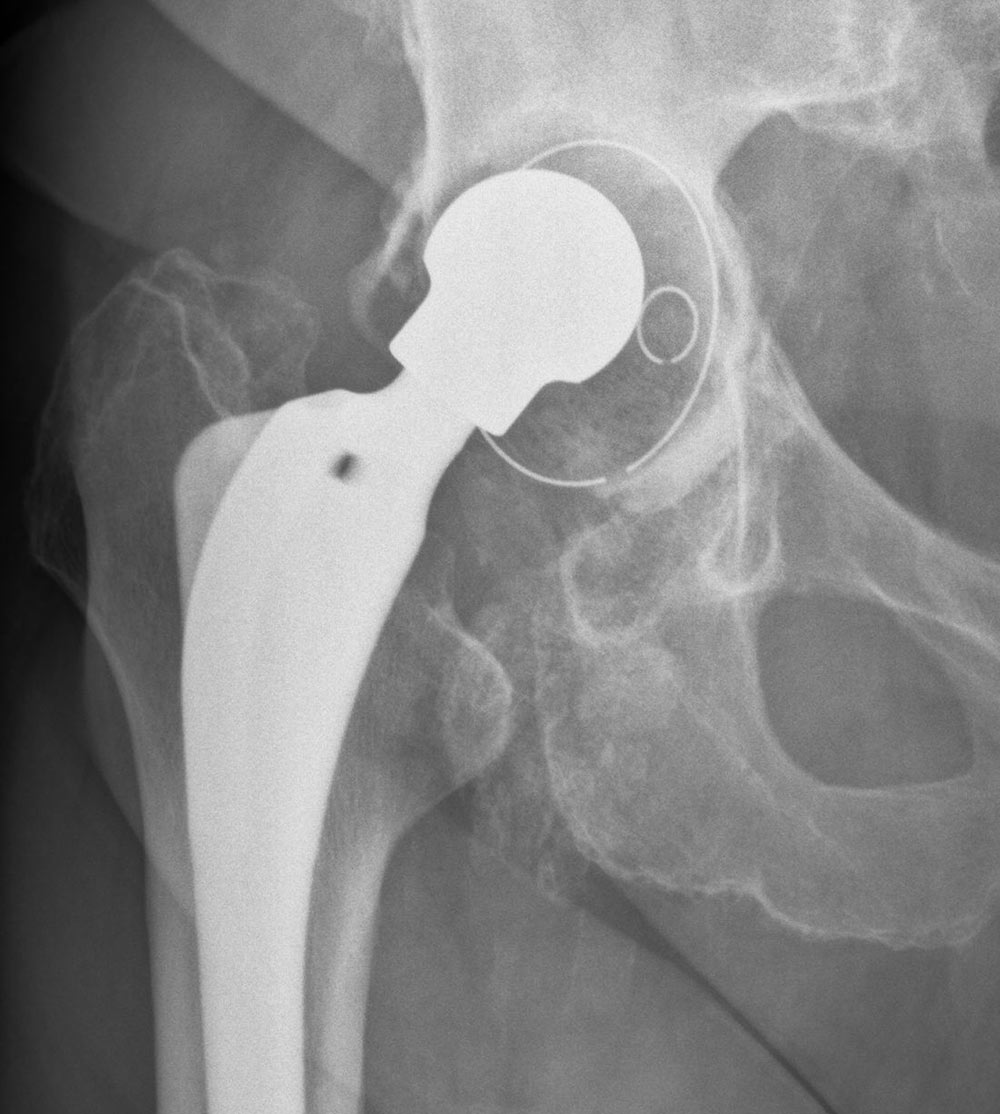

Nach der Implantation einer zementfreien Hüftprothese

Hüfte

Röntgenbild Pfannenlockerung

Röntgenbild Zustand nach Wechseloperation mit Pfannendachschale

12 Jahre nach Wechsel einer Hüftprothese

12 Jahre nach Wechsel einer Hüftprothese